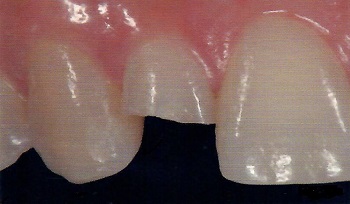

The detection of carious lesions and cracks at an early stage is necessary in order to implement prophylactic, or minimally-invasive and pain-free treatment. In daily practice, the diagnosis of initial lesions is not always simple.

The new KaVo DIAGNOcam is the first camera system that uses the tooth's structure to verify caries diagnosis. To do this, the tooth is transilluminated utilising light of a specific wavelength (780 nm generated by a led laser) and used like a light conductor. A digital video camera records the image and displays it live on a computer screen. Carious lesions are displayed as dark shadows. With its DIFOTI technology (Digital Imaging Fiberoptic Transillumination), DIAGNOcam offers high diagnostic safety which is comparable or superior to X-ray diagnosis in many cases, in particular with regard to approximal and occlusal caries. Furthermore, it is possible to show certain kinds of secondary caries and cracks. The X-ray free device thereby allows early and very gentle caries detection.

Before